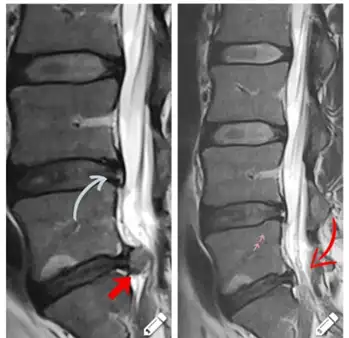

Oporavak međupršljenskih diskova L5-S1 i L5-L4 u periodu 5 jun-8 jul